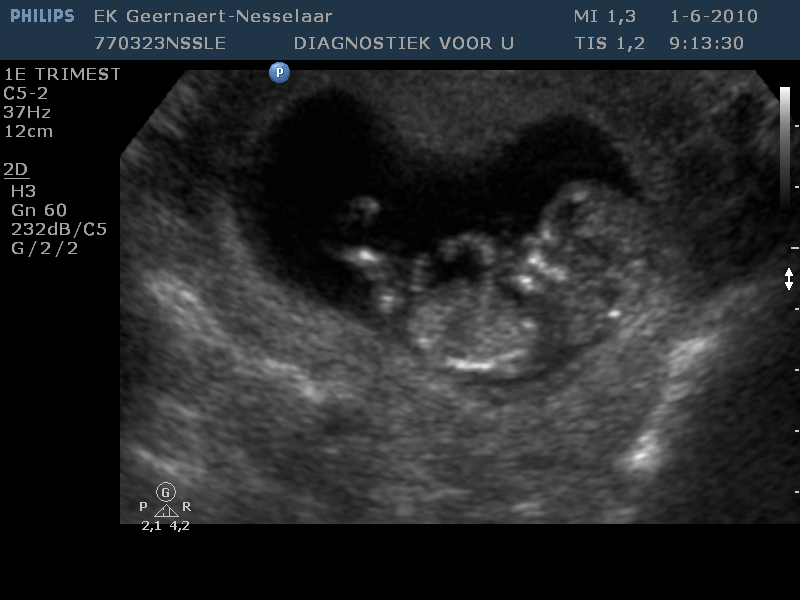

Lucas wordt grote broer!

Jawel, het is zover! Lucas wordt grote broer! Uiteraard hadden papa en mama al een klein vermoeden. Vorige week heeft de verloskundige de kleine al even laten horen, maar gister hebben we hem/haar dan ook echt mogen zien! Wat een stuiterballetje! Alles erop en eraan en heel actief, prachtig!

Met mama gaat alles vrij goed. Wat last gehad van vermoeidheid en een erg lage bloeddruk, maar ze mag niet mopperen. Het buikje begint al aardig te groeien. Tja, de boel was al een beetje opgerekt door Lucas.

Half december zal het zover zijn. We zijn benieuwd hoe Lucas het zal vinden. Hij zal dan toch de aandacht moeten delen. Ondertussen is papa al hard bezig een kamertje voor Lucas leeg te ruimen, want grote jongens hoeven niet meer in een baby-kamertje te slapen! En Lucas, die heeft nog niets in de gaten…